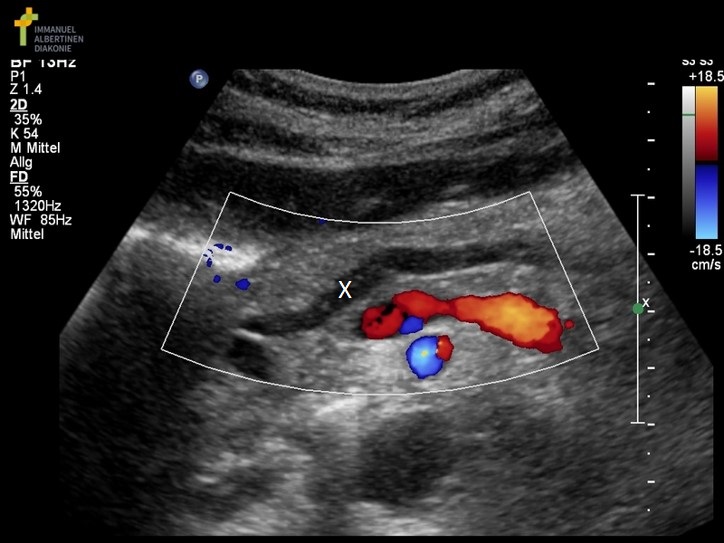

What structure is marked with the X on the image?

Main pancreatic duct

What structures/vessel is indicated by #5?

Tail of the pancreas

Which structure/vessel is indicated by #4?

Body of the pancreas

What structure/vessel is indicated by #3?

Lateral branch of LPV

What structure/vessel is indicated by #7?

Splenic vein